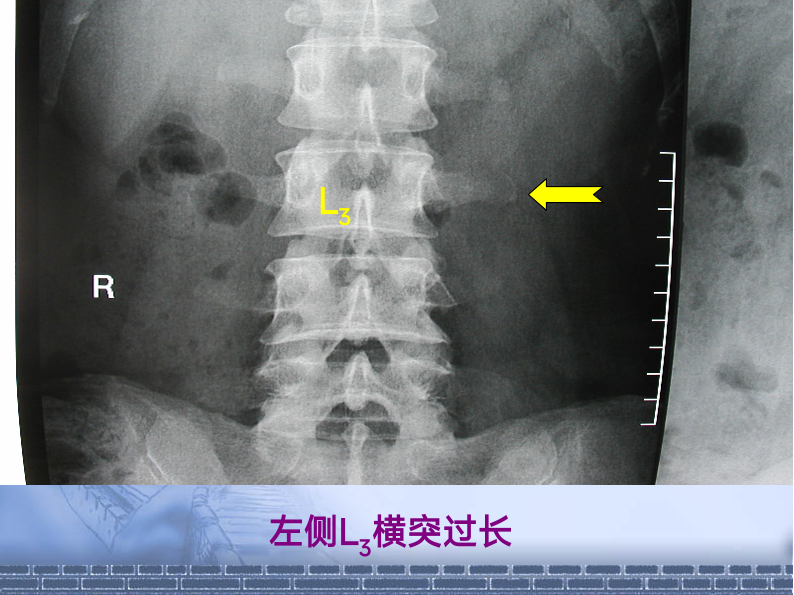

推拿治疗第三腰椎横突综合症